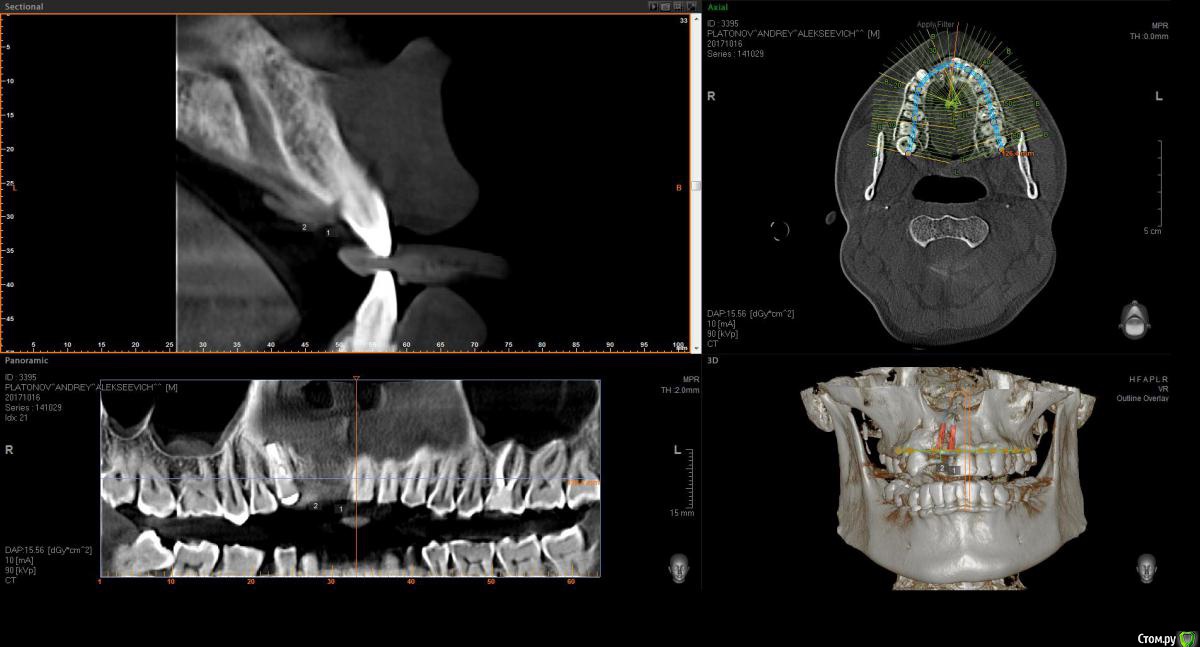

Eddie Опубликовано 23 октября, 2017 Поделиться Опубликовано 23 октября, 2017 (изменено) Здравствуйте! Подскажите по планированию имплантации. 11- удален 4-5 месяцев назад, 12-несколько лет назад. Пациент на данный момент носит съемник.как лучше позиционировать имплантаты? возможно ли обойтись без нкр, а поработать конденсорами? Еще смущает, что в области 11 возможно дефицит кости после удаления? Если ставить 11 чуть ближе к 21, то там условия по-лучше, но до 21 расстояние 1.5 мм или даже чуть меньше!В клинике только Ankylos. Реально ли будет отпротезировать при таких позициях?Буду благодарен любым советам. P.S. пациент финансово не потянет нкр Изменено 23 октября, 2017 пользователем Eddie Ссылка на комментарий

Bier Опубликовано 25 октября, 2017 Поделиться Опубликовано 25 октября, 2017 не вижу уровня гребня. Фотки бы. По тому что я вижу, имплантат в область 12 с Анкилос как раз подойдет. + десна в область 12 и 11.Если это ваш первый кейс, боюсь, что вы его запорите. Ссылка на комментарий

Eddie Опубликовано 25 октября, 2017 Автор Поделиться Опубликовано 25 октября, 2017 (изменено) не вижу уровня гребня. Фотки бы. По тому что я вижу, имплантат в область 12 с Анкилос как раз подойдет. + десна в область 12 и 11.Если это ваш первый кейс, боюсь, что вы его запорите.Спасибо за ответ. В клинике я один хирург! Отказаться вряд ли получится. Есть опыт установки имплантатов в области жевательных зубов, опыт работы с десной. Если всё-таки буду ставить, в области 12 в плане вестибуло-орального положения и наклона как лучше спозиционировать? Изменено 25 октября, 2017 пользователем Eddie Ссылка на комментарий

Bier Опубликовано 25 октября, 2017 Поделиться Опубликовано 25 октября, 2017 Нет, пациент готов еще без зуба походитьнаклон не имеет принципиального значения. Я бы ставил четко по гребню. Вестибуло-орально центр имплантата должен смотреть в слепую ямку предполагаемого зуба. Для этого начинать сверление нужно на 0,5-1мм нёбнее с давлением на нёбную стенку, чтобы имплантат в итоге не встал вестибулярно. Я бы откинул лоскут в области 12 и туннелировал офтальмологическим скальпелем область 11. Понадобятся внутрибороздковые разрезы в области 21з взять ССТ и завести его правую часть под слизистую в области 11з, а левую надеть на формик. Формирование овоида не ранее, чем через 6 недель после операции. Ссылка на комментарий